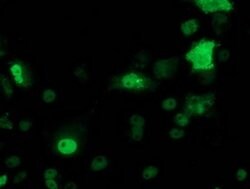

| Applications | Flow Cytometry, Immunocytochemistry, Immunofluorescence, Western Blot |